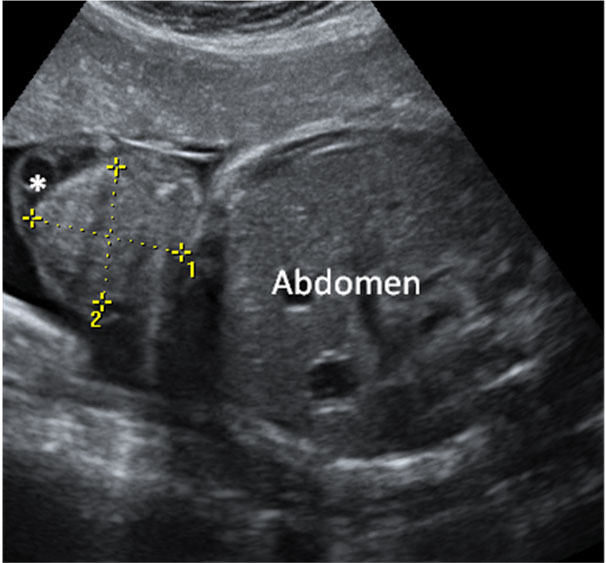

Esta imagen de una ecografía en 3D en la semana 20 de gestación al feto se le distinguen los huesos de los brazos y del cráneo, así como las fontanelas. Estas son aberturas en los huesos del cráneo que van a permitir que se superpongan cuando el bebé atraviese el canal del parto al nacer.

Si nos fijamos se nota la fontanela y los huesos craneales. También se ven de forma nítida los huesos del brazo: húmero, cúbito y radio.